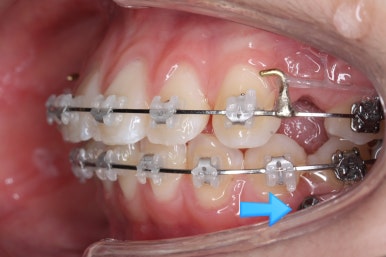

부산교정 키다리아저씨치과에 처음 내원하셨을 때의 입안 모습입니다.

윗니가 삐뚤어져 있고, 아래앞니 사이에는 틈이 듬성듬성 보입니다.

아랫니를 살펴보면 화살표 표시를 해둔 송곳니~송곳니 사이에 치아가 1개 모자랍니다. 원래는 4개의 앞니가 있어야 하는데, 3개 밖에 없었습니다. 이런 결손치아의 경우는 다음과 같은 문제가 생깁니다.